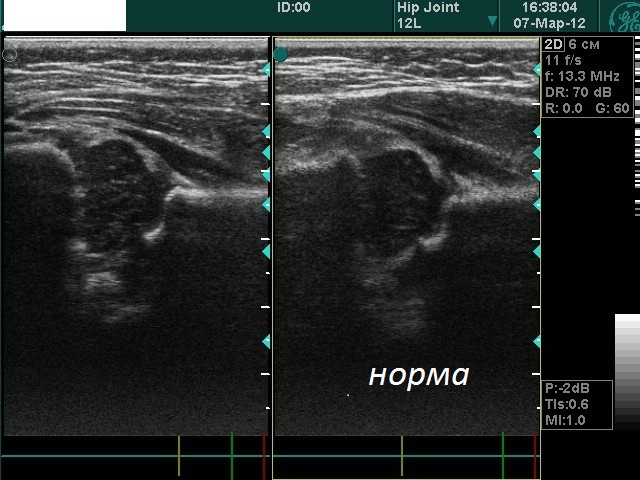

Ультрасонография тазобедренных суставов, сделанная на втором месяце лечения, показывающая созревание обоих тазобедренных суставов.

Двустороннее УЗИ зрелых тазобедренных суставов пятимесячной девочки (Пациентка №10).